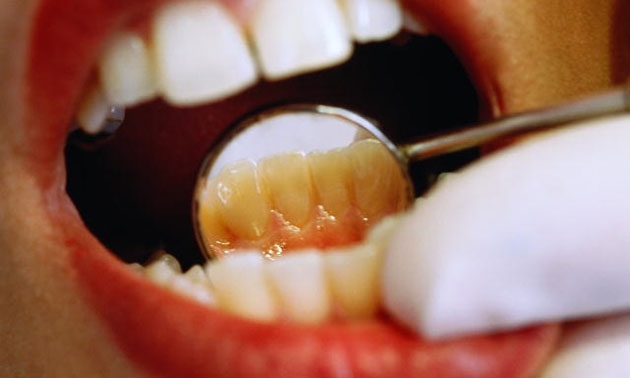

**************************ก่อนการรักษา

...